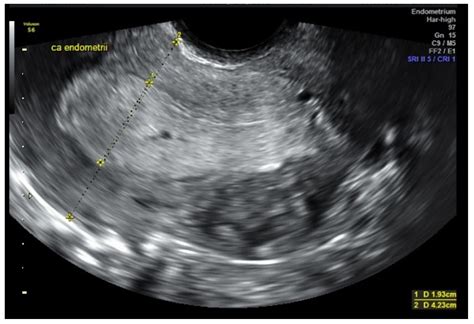

Interpreting Ultrasound Results: Measuring the Endometrial Stripe

The primary metric used during an Endometrial Cancer Ultrasound is the thickness of the endometrial stripe. Doctors measure the thickest part of the lining in a longitudinal plane. While thresholds can vary based on individual risk factors, general guidelines exist to help guide clinical decision-making.

Postmenopausal (with bleeding) 4-5 mm or less Low risk; observation may be sufficient.

Postmenopausal (with bleeding) Greater than 5 mm Further investigation (biopsy) recommended.

It is important to emphasize that these measurements are guidelines, not absolute rules. A thin endometrium does not completely rule out malignancy, and a thick endometrium does not automatically mean cancer is present. Conditions such as benign polyps, hormone replacement therapy usage, or hormonal imbalances can also cause the lining to appear thickened.